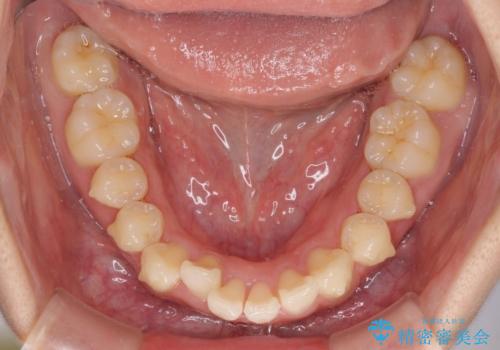

上下前歯の叢生をインビザラインできれいに

- 前歯のデコボコを気にして来院された患者様です。

前歯が重なっていることで口元が閉じにくくなっていたため、歯列全体の側方への拡大と、歯と歯の間を少し削ってスペースを獲得することとしました。

下顎前歯は後戻りを起こしやすいため、舌側を細いワイヤーで固定し、マウスピース型リテーナーで保定を行うこととしました。